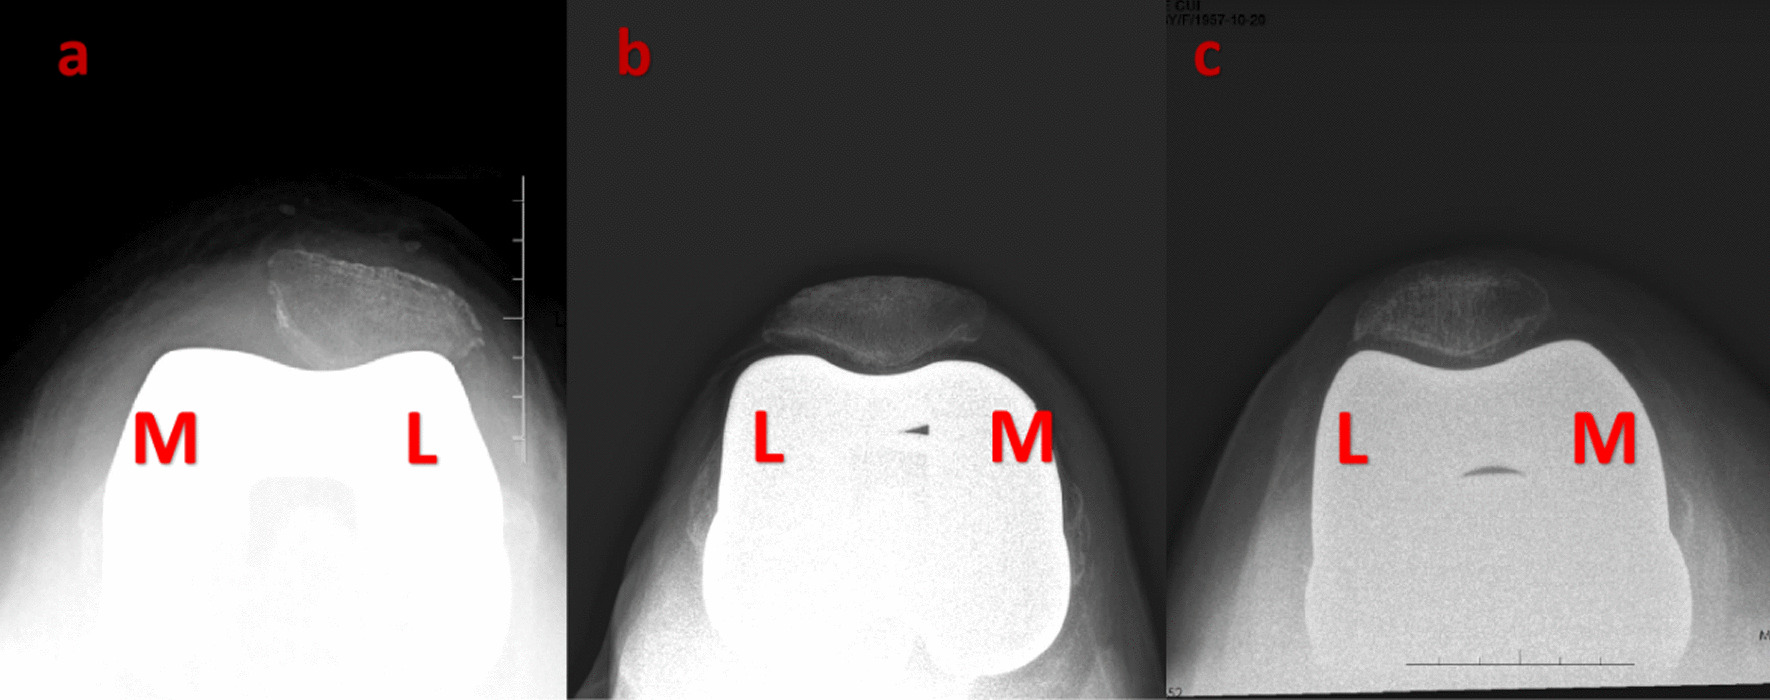

Fig. 3.

Postoperative follow-up axial patellar X-rays. a. Genesis II b. Triathlon c. Gemini MK II. Abbreviations: M, medial; L lateral